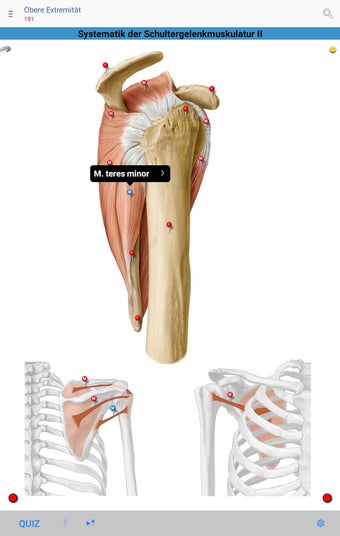

The app consists of different sections, each of which contains information about a specific part of the body. You will learn about the different organs, as well as the muscles, bones, and other important structures. You can test yourself with a unique quiz that consists of multiple-choice questions.